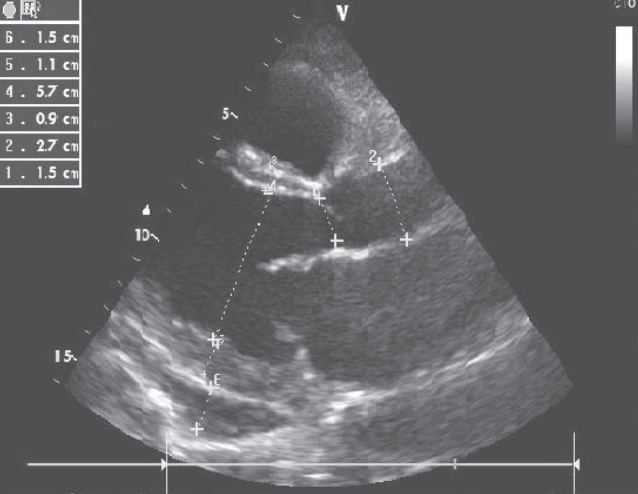

心脏超声:左心室扩张,左心室舒张末期内径57 mm,左心室收缩末期内径51 mm,左心室弥漫性运动减弱,LVEF=15%;限制性舒张功能障碍(E/E‘=19),二尖瓣、三尖瓣反流,中度肺动脉高压(图2)。

图2 心脏超声结果